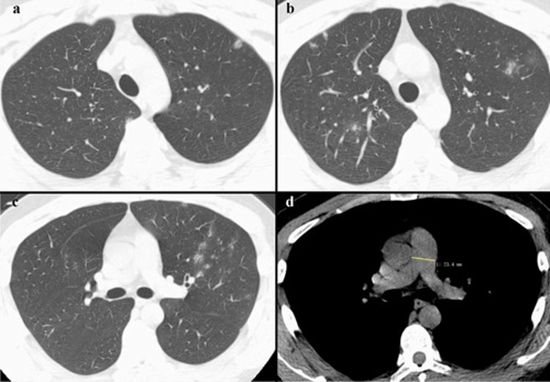

دراسة الترابط بين قطر الجذع الشرياني الرئوي حسب التصوير المقطعي المحوسب وشدة ارتفاع ضغط الشريان الرئوي في تخطيط صدى القلب، ومستوى NT-ProBNP في الدم لدى المرضى المصابين بارتفاع ضغط الشريان الرئوي خلال عامي 2019-2020 في مستشفى الإمام الخميني بطهران

همبستگی بین دیامتر تنه شریان ریوی درct و شدت هیپرتانسیون آن در اکوکاردیوگرافی